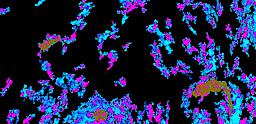

Pancreatic ductal adenocarcinoma is a lethal disease with limited treatment options and poor survival. We studied 83 spatial samples from 31 patients (11 treatment-naïve and 20 treated) using single-cell/nucleus RNA sequencing, bulk-proteogenomics, spatial transcriptomics and cellular imaging. Subpopulations of tumor cells exhibited signatures of proliferation, KRAS signaling, cell stress and epithelial-to-mesenchymal transition. Mapping mutations and copy number events distinguished tumor populations from normal and transitional cells, including acinar-to-ductal metaplasia and pancreatic intraepithelial neoplasia. Pathology-assisted deconvolution of spatial transcriptomic data identified tumor and transitional subpopulations with distinct histological features. We showed coordinated expression of TIGIT in exhausted and regulatory T cells and Nectin in tumor cells. Chemo-resistant samples contain a threefold enrichment of inflammatory cancer-associated fibroblasts that upregulate metallothioneins. Our study reveals a deeper understanding of the intricate substructure of pancreatic ductal adenocarcinoma tumors that could help improve therapy for patients with this disease.